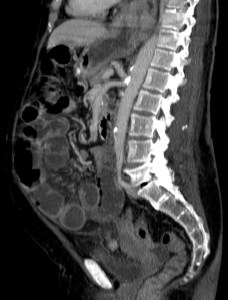

Se realiza TC de abdomen en vacío y con contraste en fase portal:

Estamos ante un cuadro de isquemia intestinal en un paciente con bajo gasto cardiaco con afectación principal de asas intestino delgado, territorio vacularizado por la arteria mesentérica superior.

- Las imágenes sagitales son útiles para evaluar el origen de las arterias mesentéricas y sus variaciones.